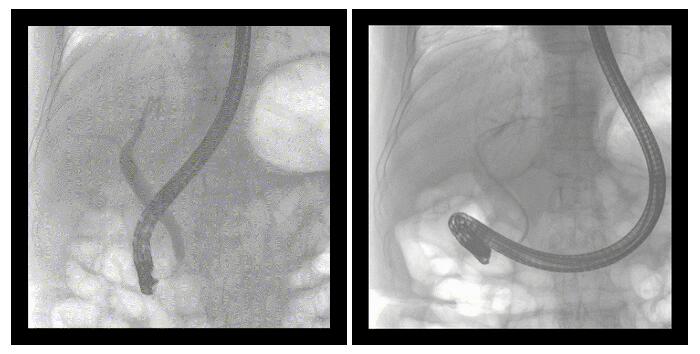

移动式平板中C术中影像

普爱医疗http://www.pl999.com/class.php?anclss=1&nclass=29移动式平板中C为本次ERCP手术提供实时无损高清影像,帮助医生准确定位。“成像效果非常棒!完全不输国际品牌的医学影像设备……”鼓楼医院江北国际医院内镜中心手术团队对普爱医疗移动式平板中C的成像效果给与了高度的评价。

近日,一位86岁的女性患者近来出现腹痛,入院后CT检查并结合临床表现被诊断为急性胆囊炎伴胆囊结石。经专家团队协商并与患者家属沟通,决定对患者实施经内窥镜逆行胰胆管造影(ERCP)。南京鼓楼医院江北国际医院内镜中心团队在普爱医疗移动式平板中C(ERCP专用)的引导下成功完成这次ERCP手术。